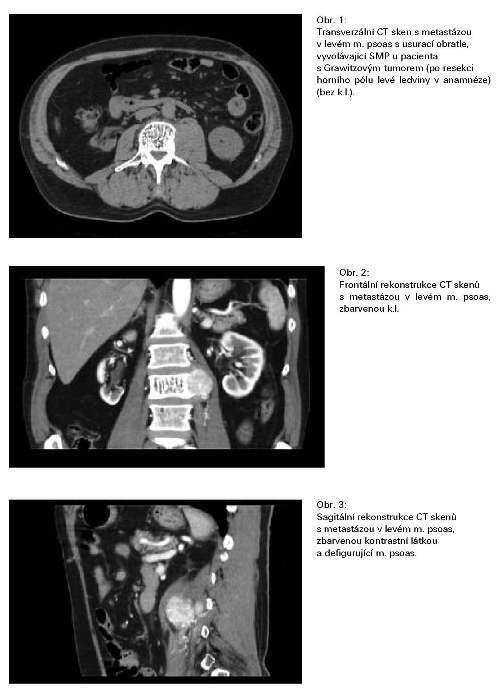

Nejvíce pacientů se SMP bylo nalezeno u maligních nádorů ledviny - 5, tj. v 1,6% (5/312), primární léčba byla vždy chirurgická - nefrektomie, v případě rozsahu T3 byli pacienti do r. 1998 ozářeni na oblast lůžka ledviny a paraaortálních uzlin, v dalších letech pacienti obdrželi imunoterapii nebo chemoimunoterapii. U pacientů se SMP radioterapie v primární léčbě nebyla. Infiltrace psoatu souvisela ve 4 případech (4/5) s recidivou v oblasti lůžka odoperované ledviny a/nebo metastatickým procesem paraaortálních uzlin, u 1 pacienta s metastázou v m. psoas (obr. 1., 2., 3.)